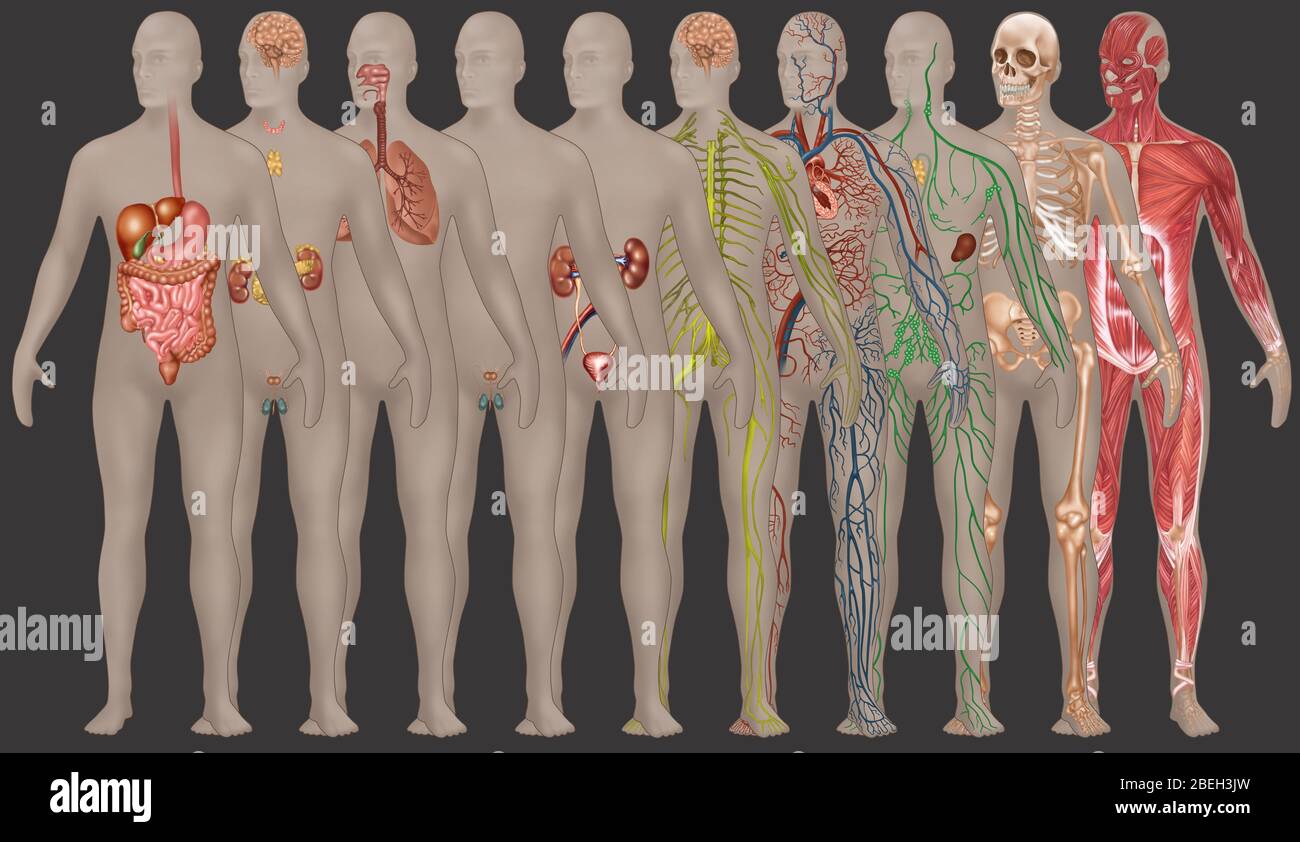

Suchergebnisse für Männchen anatomie Stock-Fotos & Bilder (86,080)